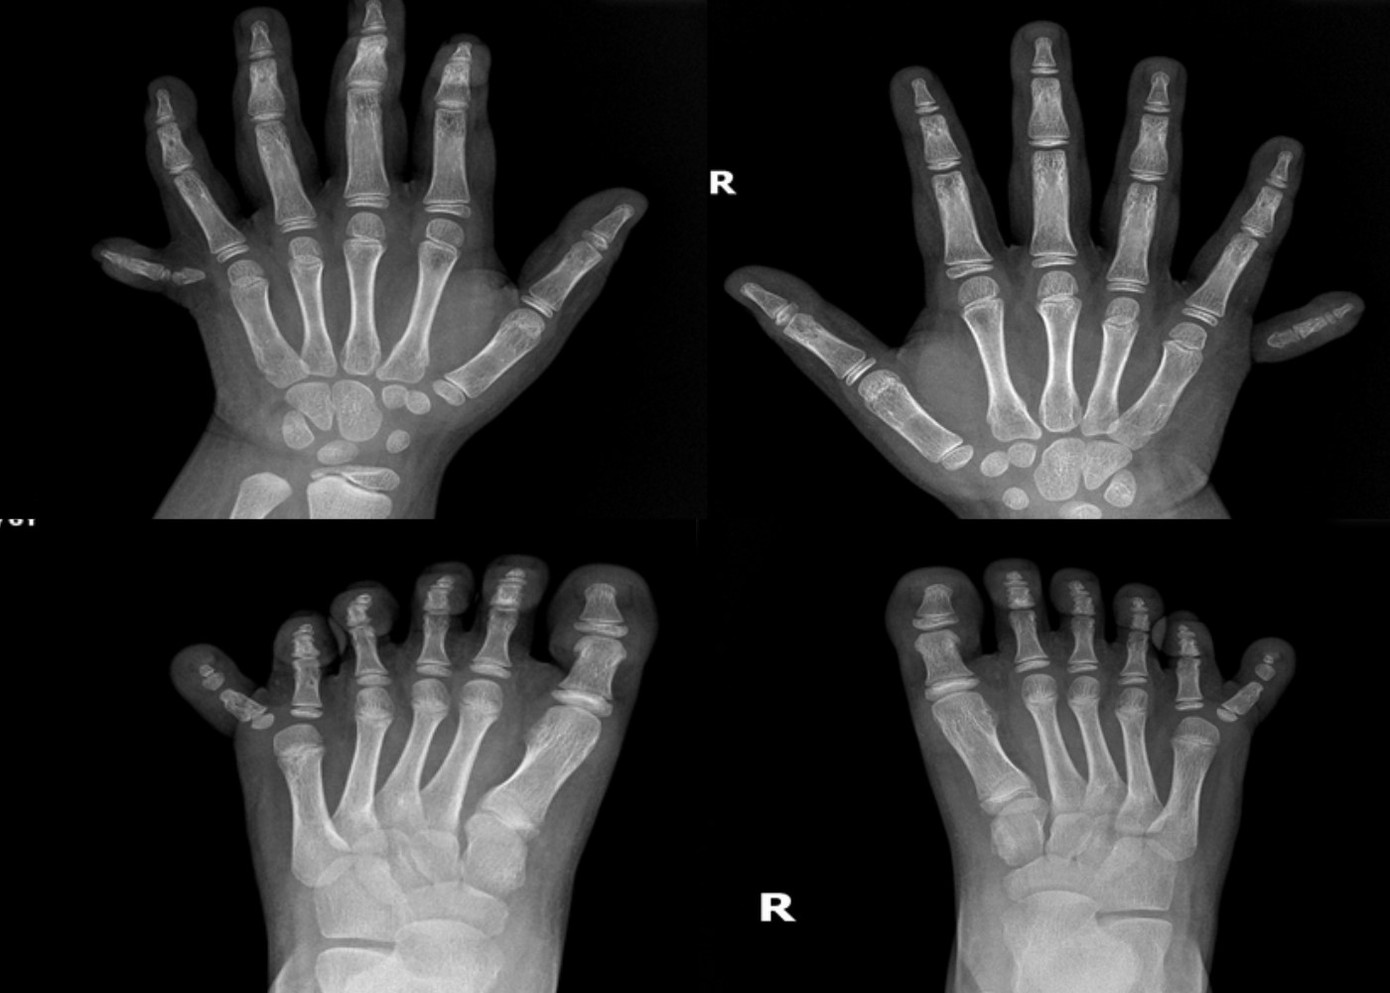

| Bàn tay, chân của bé đều 6 ngón. |

Ngày 27/6, chị H.M., mẹ của bé L. đưa bé đến bệnh viện để thăm khám và bày tỏ mong muốn thực hiện phẫu thuật để loại bỏ những ngón tay, chân thừa cho bé. Mỗi bàn tay, bàn chân của bé L. đều có 6 ngón. Mặc dù các ngón tay chân vẫn phát triển và có xương bình thường nhưng việc dư thừa các ngón khiến cho sinh hoạt của em bị cản trở, đặc biệt là khi lựa chọn giày, vận động, chạy nhảy.

Theo bác sĩ CKI Huỳnh Đắc Anh, dị tật thừa ngón là tình trạng bẩm sinh khi có ngón tay hoặc ngón chân thừa (nhiều hơn 5 ngón), gặp phải ở khoảng 2/1000 trẻ sơ sinh. Tuy nhiên, sự xuất hiện đồng thời của dị tật thừa ngón ở cả tứ chi cùng lúc là một trường hợp cực kỳ hiếm gặp, chỉ với một số ít trường hợp được báo cáo trên toàn thế giới.